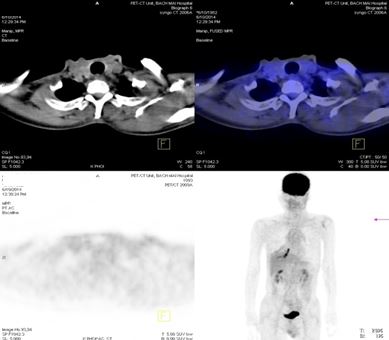

Trước điều trị: Hạch thượng đòn phải 1,1cm, max SUV=5,67; Hạch thượng đòn trái 0,8cm, max SUV=3,97.

Sau điều trị: Không thấy hạch thượng đòn

Trước điều trị: Tổn thương cung sau xương sườn số 2 bên phải, giá trị max SUV=3,13.

Sau điều trị 4 tháng: Không có bất thường

8.Đánh giá sau 9 tháng điều trị:

Lâm sàng đáp ứng tốt, bệnh nhân không còn nổi ban ngoài da, chụp PET/ CT đánh giá lại sau 9 tháng điều trị kết quả: khối u phổi phải không còn, không còn hạch di căn, các vị trí di căn tại gan, xương biến mất.

Trước điều trị ( T2/ 2014)

Sau điều trị 9 tháng ( T11/ 2014)